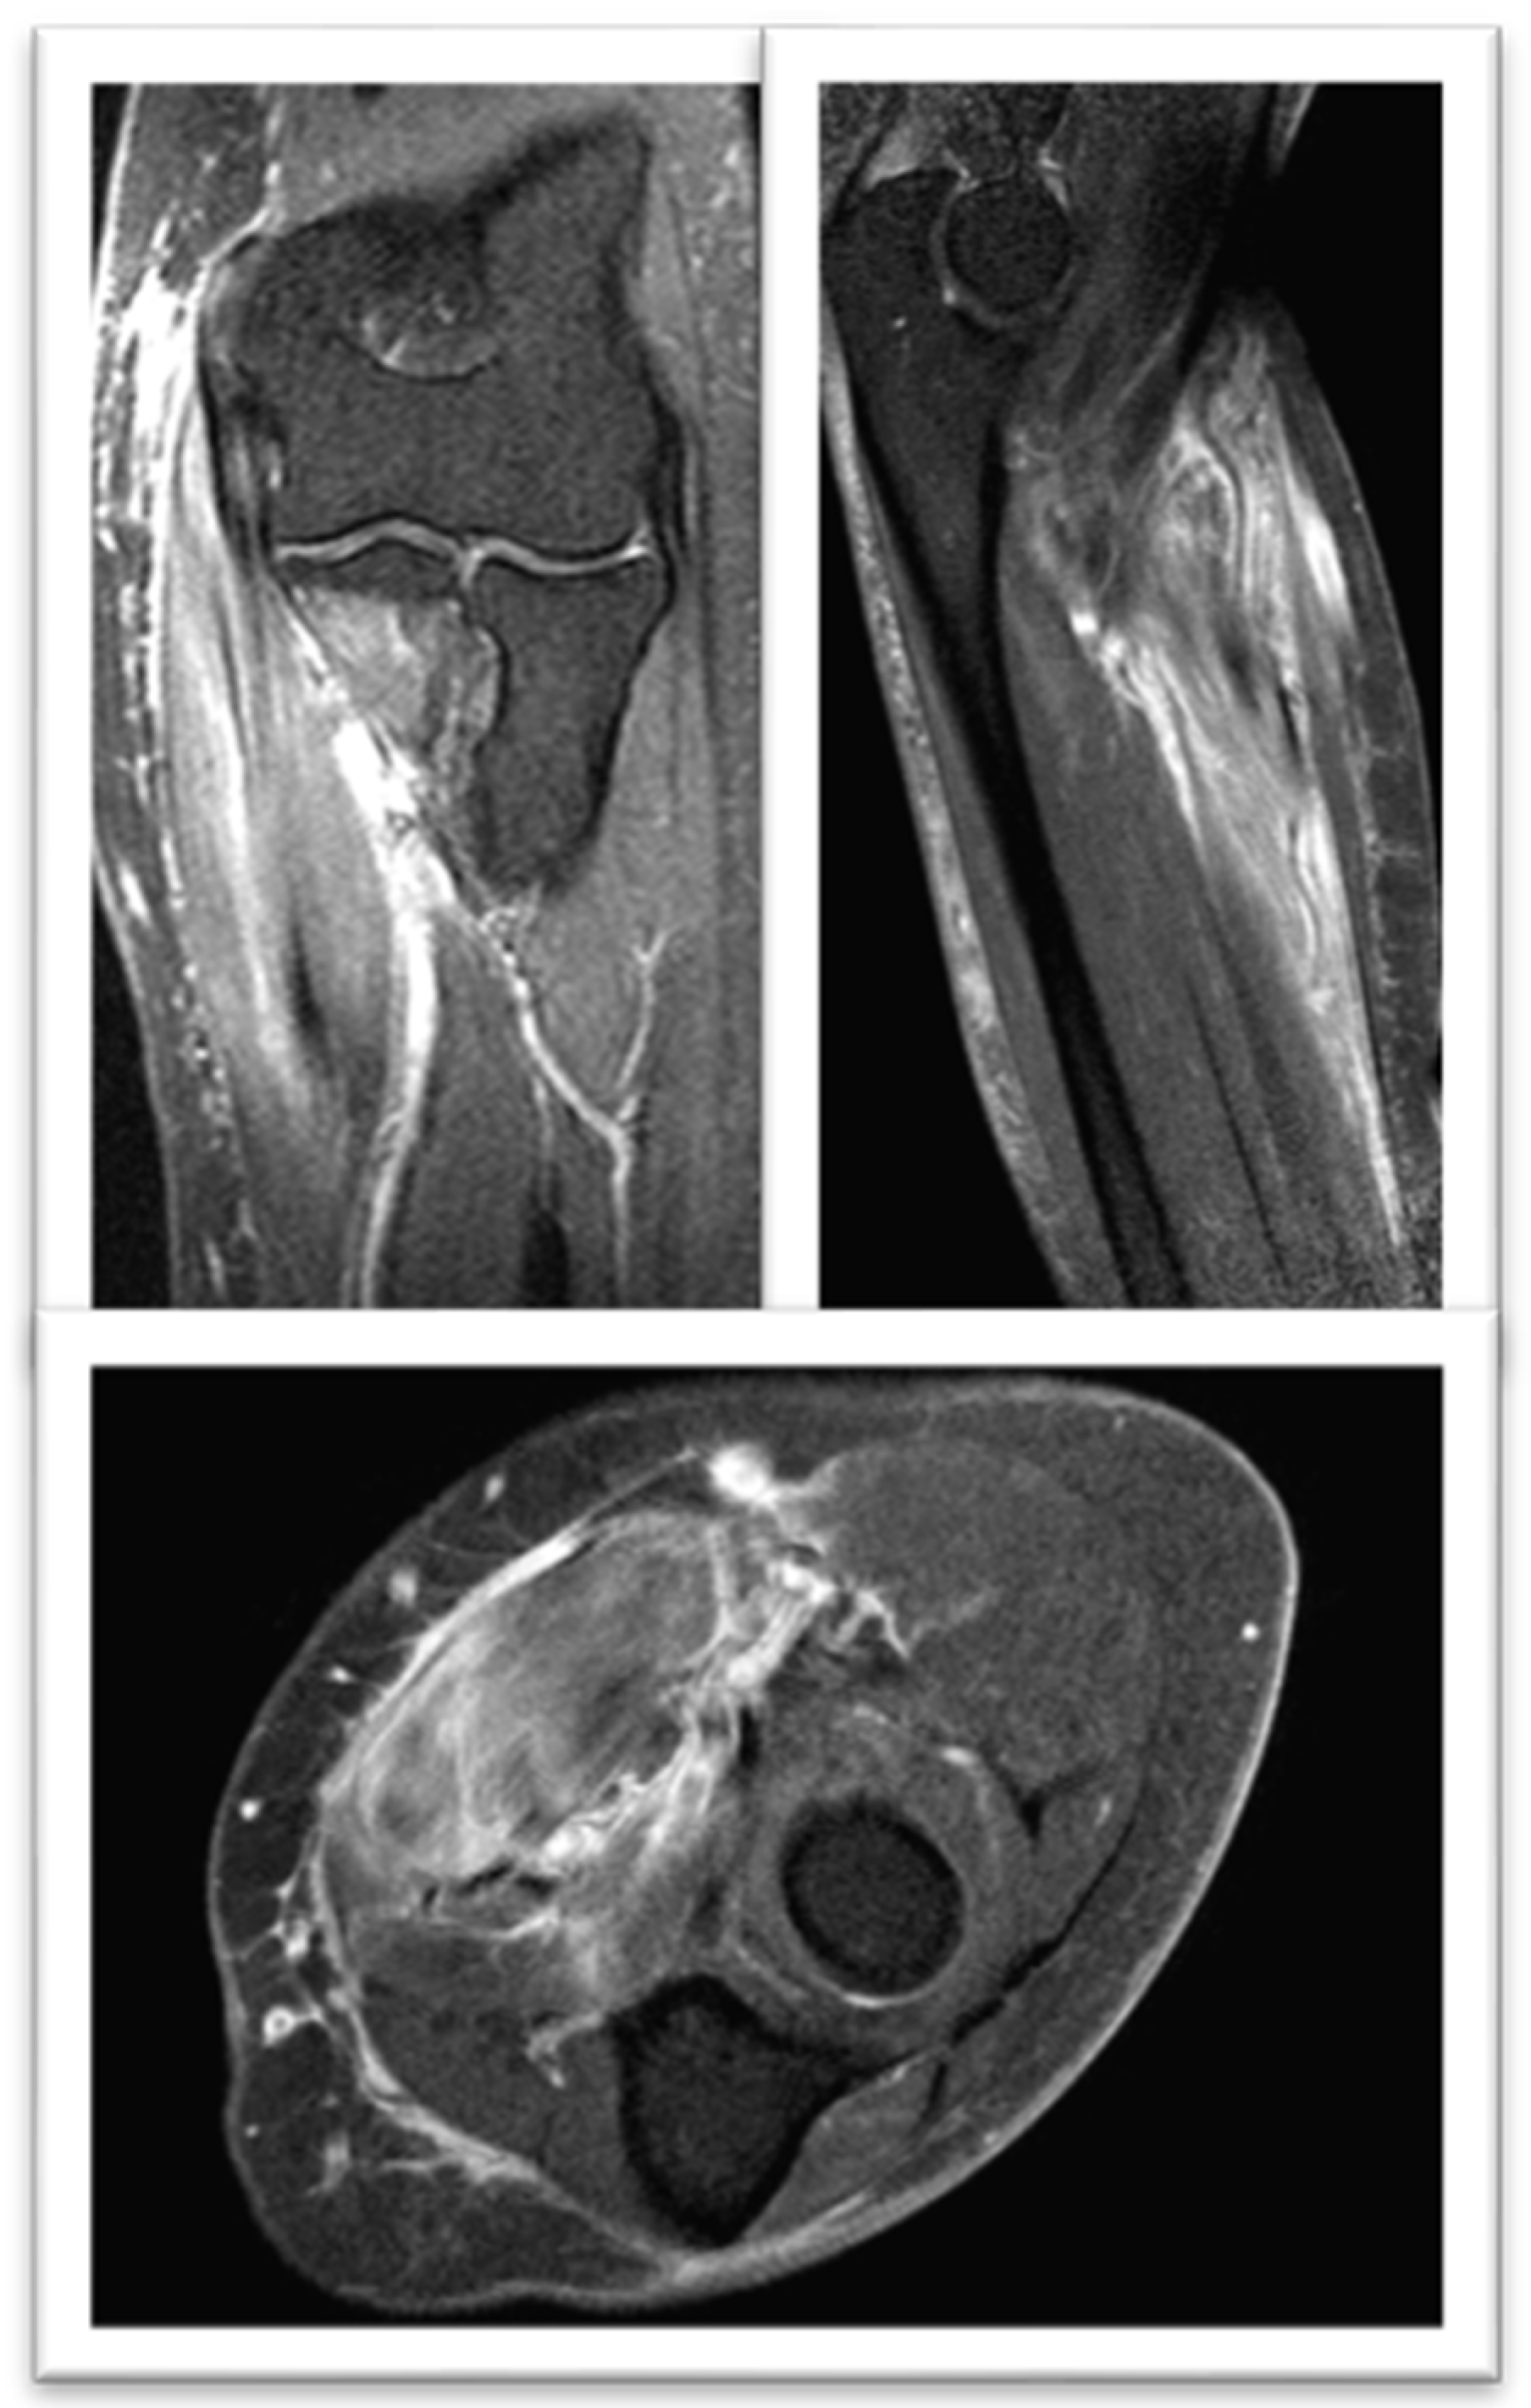

2. Case Report